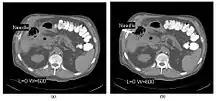

- CT Fluoroscopy (CTF) has also been referred to as Continuous CT or Real-Time CT since it involves generating tomographic images at sufficiently high frame rates to allow guidance of needle placement in small or deep-seated lesions. Applications can include biopsy of thoracic lesions, biopsy/drainage of pelvic lesions, vertebroplasty and drainage/aspiration of intracranial haematomas. The advantages of CTF include increased target accuracy and reduced procedure times[45].

- The value of N is typically 30o, 45o or 60o, with frame rates of 12, 8 and 6 frames per second, respectively. In the case of 60o updates and 6 frames per second, the delay between each image is 0.17 seconds. A Last-Image-Hold (LIH) technique can be used while the image is being updated with the resulting time lag being considered by the interventionist in terms of biopsy technique. Example images are shown in Figure 7.15.11. The display of three adjacent slices of thickness 5 mm with MDCT scanning can be used to improve visual feedback to the interventionist as the needle progresses. In addition, multi-planar reconstructions (MPR) and volume rendered 3D images can be used to enhance fine control.